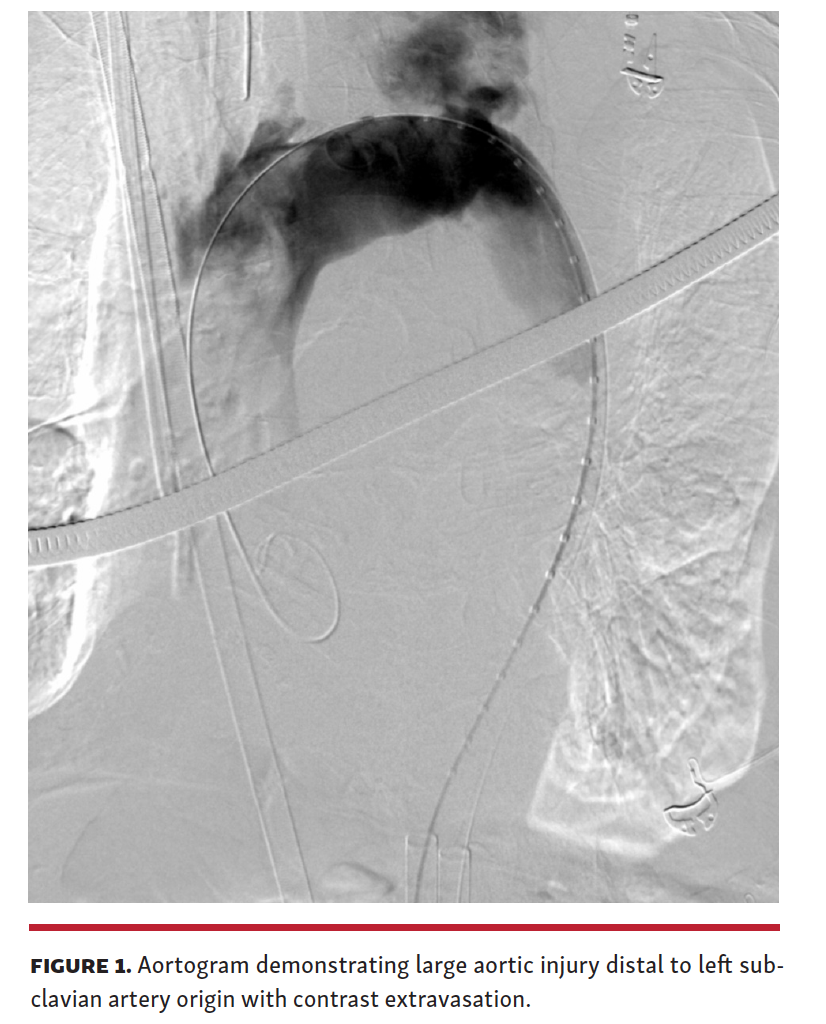

A 95-year-old man with severe symptomatic aortic stenosis was admitted for elective transcatheter aortic valve replacement (TAVR). He had balloon aortic valvuloplasty 1 year prior with aortic valve restenosis resulting in dyspnea on minimal exertion. The patient pursued TAVR for improvement in quality of life. His preprocedure computed tomography (CT) scan demonstrated moderate aortic and iliofemoral atherosclerosis. TAVR was performed in a hybrid theater with bilateral femoral arterial access. After crossing the aortic valve and recording peak-to-peak aortic valve gradient of 48 mm Hg, a stiff wire was placed in the left ventricle. The valve delivery system was passed over this, but would not easily cross the aortic arch. The patient became distressed and hypotensive. The aortogram demonstrated large aortic injury distal to the left subclavian artery origin with significant extravasation (Figure 1 and Video 1). The patient had pulseless electrical activity. Despite cardiopulmonary resuscitation, rapid blood transfusion, and covered stenting of aortic injury, the patient did not survive.